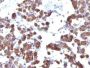

Thyroglobulin is a 660 kDa dimeric pre-protein with mutiple glycosylation sites. It is produced by and processed within the thyroid gland to produce the hormone thyroxine and triiodothyronine. Prior to forming dimers, thyroglobulin monomers undergo conformational maturation in the endoplasmic reticulation. The vast majority of follicular carcinomas of the thyroid will give positive immunoreactivity for anti-thyroglobulin even though sometimes only focally. Poorly differentiated carcinomas of the thyroid are frequently anti-thyroglobulin negative. Adenocarcinomas of other-than-thyroid origin do not react with this antibody. This antibody is useful in identification of thyroid carcinoma of the papillary and follicular types. Presence of thyroglobulin in metastatic lesions establishes the thyroid origin of tumor. Anti-thyroglobulin, combined with anti-calcitonin, can identify medullary carcinomas of the thyroid. Furthermore, anti-thyroglobulin, combined with anti-TTF1, can be a reliable marker to differentiate between primary thyroid and lung neoplasms.Primary antibodies are available purified, or with a selection of fluorescent CF® Dyes and other labels. CF® Dyes offer exceptional brightness and photostability. Note: Conjugates of blue fluorescent dyes like CF®405S and CF®405M are not recommended for detecting low abundance targets, because blue dyes have lower fluorescence and can give higher non-specific background than other dye colors.

Positive Control

Thyroid

IHC, FFPE (verified)

IHC (FFPE) (verified)

Higher concentration may be required for direct detection using primary antibody conjugates than for indirect detection with secondary antibody|Immunohistology formalin-fixed 0.1-0.2 ug/mL|Staining of formalin-fixed tissues requires boiling tissue sections in 10 mM citrate buffer, pH 6.0, for 10-20 min followed by cooling at RT for 20 minutes|Flow Cytometry 0.5-1.0 ug/million cells in 0.1 mL|Optimal dilution for a specific application should be determined by user